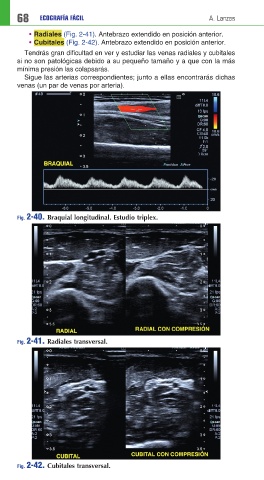

• Radiales (Fig. 2-41). Antebrazo extendido en posición anterior.

• Cubitales (Fig. 2-42). Antebrazo extendido en posición anterior.

Fig. 2-40. Braquial longitudinal. Estudio triplex.

Fig. 2-41. Radiales transversal.

Fig. 2-42. Cubitales transversal.